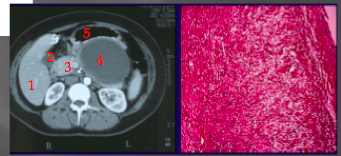

pancreatic pseudocyst